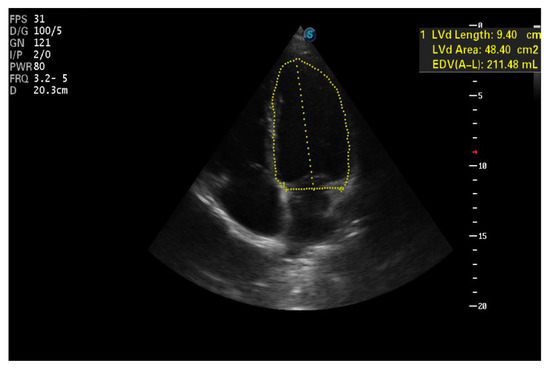

| IVS (cm)—PLAX | 1.93 | 1.27 | 1.2 |

| PLVW (cm)—PLAX | 1.38 | 1.16 | 1.05 |

| RV diameter (cm)—PLAX | 4.1 | 3.7 | 3.59 |

| LVTDV (ml/m2bs)—A4C | 114.5 | 100.7 | 90.8 |

| LVTSV (ml/m2bs)—A4C | 63.8 | 54.07 | 50.9 |

| LVEF (%)—A4C | 43 | 46 | 44 |

| RVTDV (ml/m2bs)—A4C | 33.3 | 50.5 | 22.2 |

| RVTSV (ml/m2bs)—A4C | 15 | 20.6 | 13.5 |

| LATSV (ml/m2bs)—A4C (*) | 38.2 | 44.5 | 37.1 |

| RATDS (ml/m2bs)—A4C (*) | 22.7 | 50 | 10.4 |